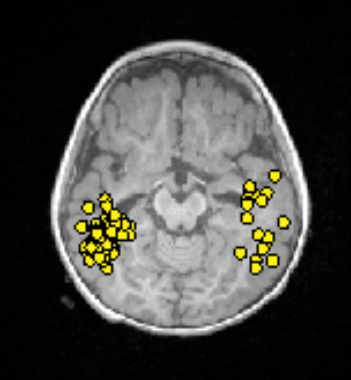

Magnetoencephalography (MEG) is a test that measures the tiny magnetic fields produced by electrical activity in the brain. Every time a group of neurons fires, it creates a small magnetic pulse. MEG detectors are sensitive enough to pick up these pulses from outside the skull.

In some ways MEG is similar to an EEG, which measures the same electrical activity using electrodes on the scalp. The difference is that magnetic fields travel through the skull and scalp without being distorted, whereas electrical signals are blurred by the time they reach the scalp electrodes. This means MEG can often pinpoint the source of abnormal brain activity more precisely than a standard EEG.

During the test, your child sits or reclines with their head positioned inside a large helmet-shaped device lined with several hundred sensors. The test is completely non-invasive — there are no needles, no injections, and no radiation. The recording typically takes one to two hours. Because the sensors need to detect extremely faint magnetic fields, the room is specially shielded from outside interference, and your child will need to stay reasonably still.

MEG is only available at a small number of specialized centers. When it is available, it is most useful in children with a normal or unclear MRI, or when other tests have not agreed on where the seizures are coming from.

Figure 10.3: MEG dipoles overlayed on MRI. Each yellow dot corresponds to localization of a single discharge.